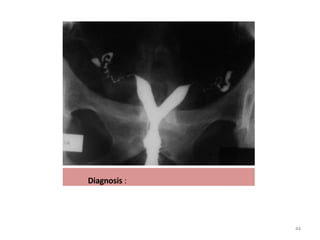

Diagnosis :